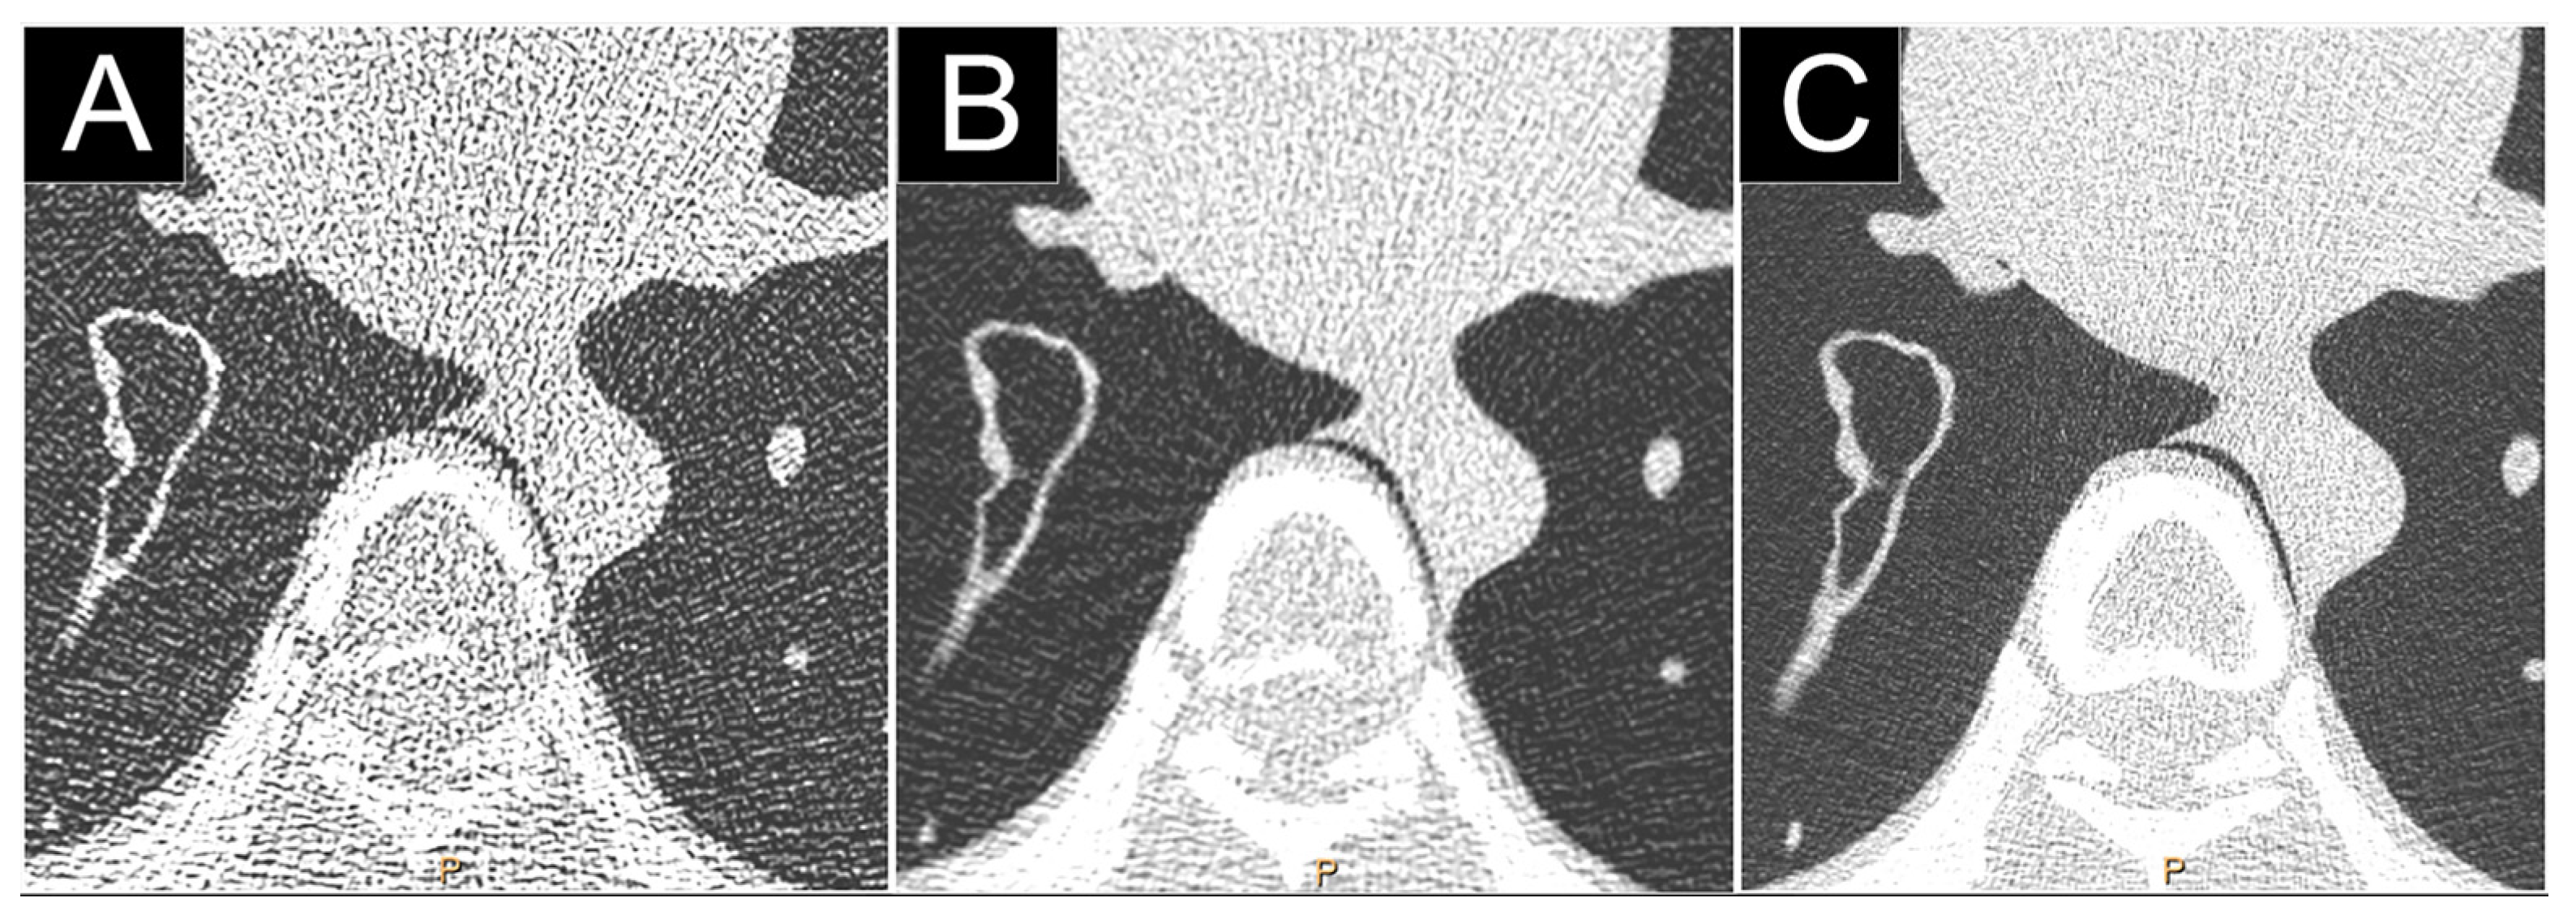

2.2.2. Reduction of Electronic Noise

3.3. Lung Cancer Screening Imaging

3.4. Low and Ultra-Low Dose Imaging